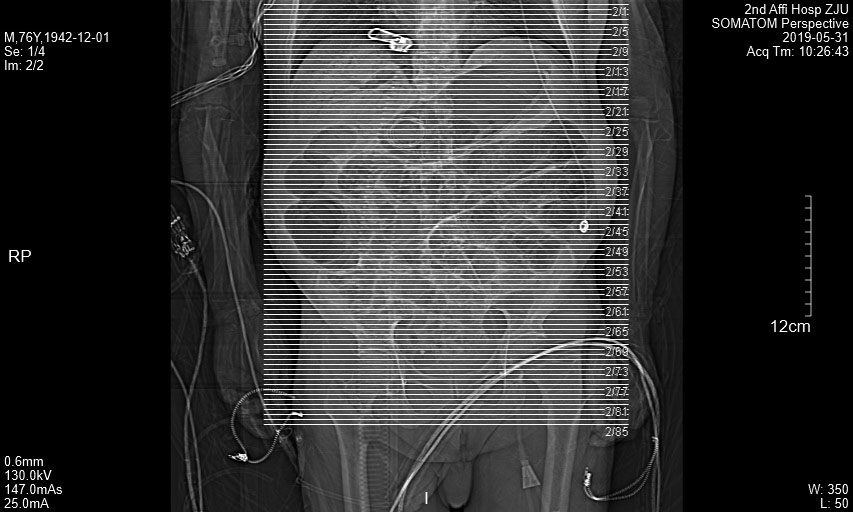

患者冠状面CT动图.gif

附图2  患者冠状面CT图